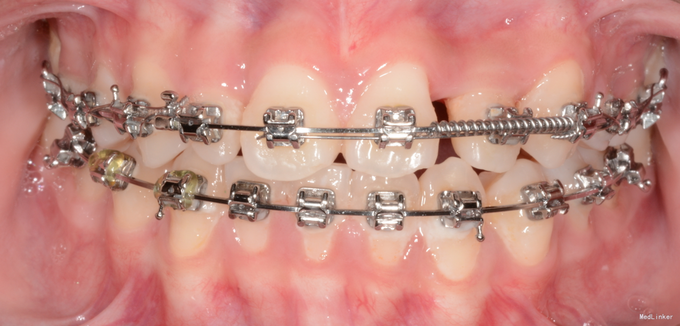

诊断:先天缺牙;22牙埋伏阻生 治疗:排齐整平后,拔除乳侧切牙(先保留乳牙不拔的目的是为了保持骨量)然后开窗牵引恒2,先用弹力线逐渐加力,牙齿快移入牙弓的时候粘接拖槽,用12niti的辅弓辅助22牙排齐,同时主弓丝仍为1825ss维持弓形不变。

目前此患者已进入精细调整阶段,效果不错。对阻生牙的牵引一般都要求在硬丝上才行,以免将弓形拉塌陷,后期快拉到位的时候,辅弓是个很好的选择,能快速排齐牵引的牙齿,同时主弓丝又能维持弓形的完整。